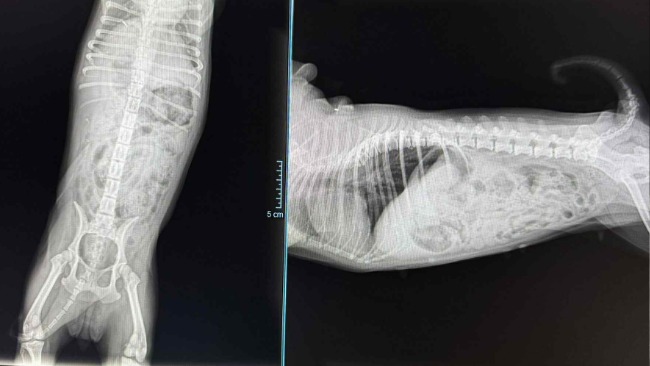

Już na pierwszy rzut oka coś nas zaniepokoiło. Jej chód był nienaturalny, chwiejny, a tylna łapka układała się w dziwny sposób.

Podejrzewamy zwichnięcie rzepki w prawym kolanie.

Przed Oliwką konsultacja ortopedyczna, która pozwoli określić stopień uszkodzenia i zaplanować leczenie, zanim ból odbierze jej radość z poruszania się.